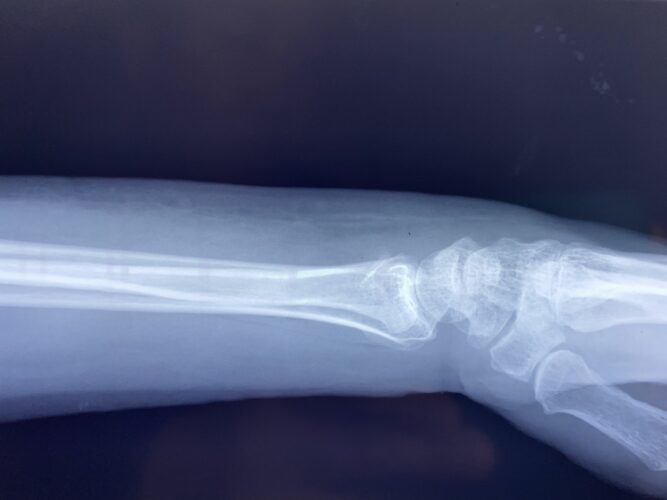

さわやか千葉県民プラザ(前腕骨下端部骨折)